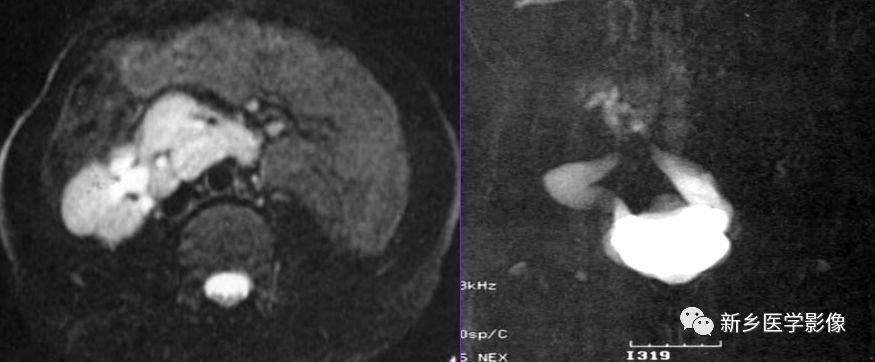

MR

肾不发育,仅为一小块肾脏,常误诊为孤立肾。多囊性肾发育不良,一侧肾区大小不等的囊肿液性水样信号,有薄厚不一的分隔,可伴发育不良肾结构,增强无强化,对侧肾和输尿管可正常。

讨论

肾发育不良与发育不全的临床表现取决于其累及的程度。常伴其他血管发育异常,检查应避免疏漏。诊断中,发现小肾结构非常重要。